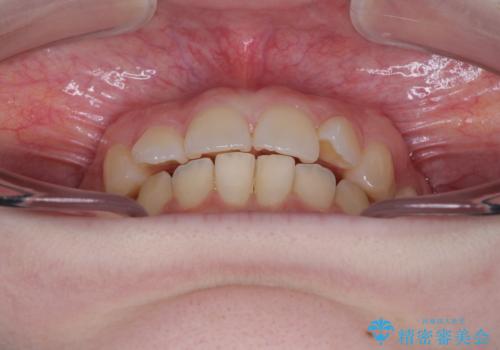

- 左上の前歯が出ていることを主訴として来院された患者様です。

当初はインビザラインを希望されていましたが、職業柄お茶する機会が多く装着時間を確保することが難しいとのことで、相談の上ワイヤー矯正の中では目立ちにくい審美装置で矯正を進めていくこととしました。

1年と少しで矯正治療を終えることができ患者様は大変満足されました。